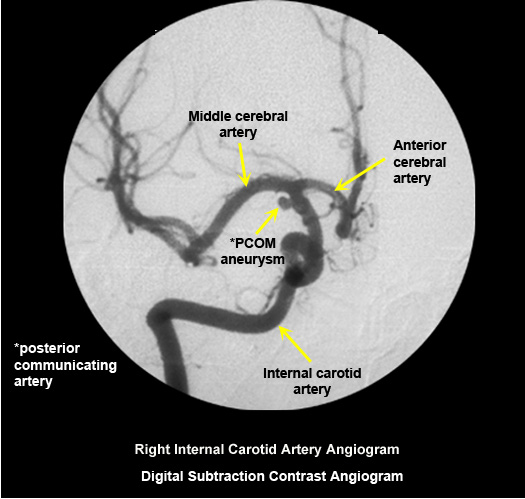

Normal digital subtraction contrast angiogram

Arterial puncture required.

Selective intra arterial contrast injection into right internal carotid artery. |